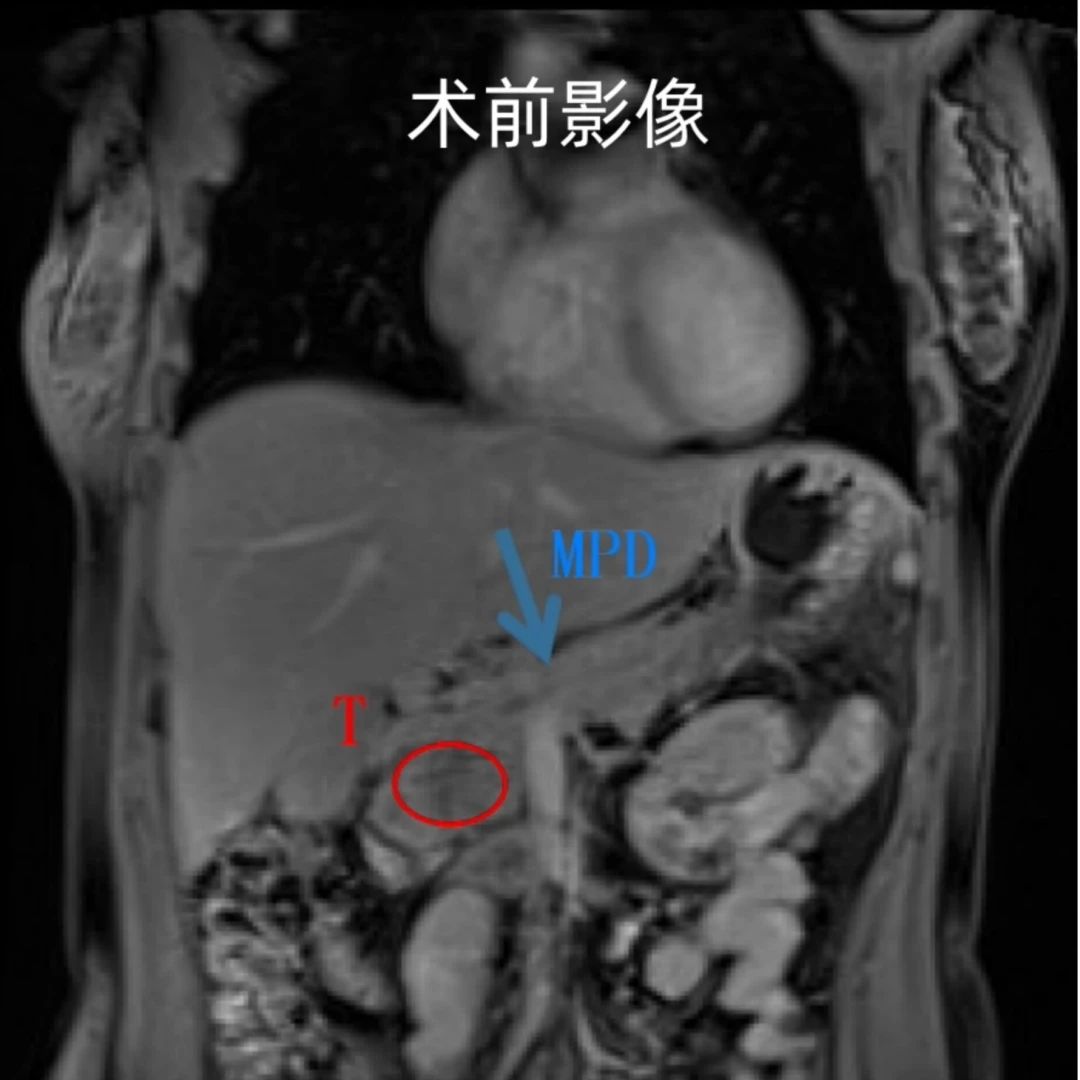

十八岁花样少女小赵(化名)跑步后突发左上腹痛,入院后经过仔细检查,发现胰体有一个约15cm*13cm的巨大肿瘤,考虑实性假乳状头状瘤,术前影像提示肿瘤与左肾、左肾上腺、左肾动静脉关系密切,侵犯脾动静脉,肿瘤压迫区域血管导致静脉严重曲张,手术难度大、术中出血风险极高,按照传统观念需要行开放胰体尾脾切除,左上腹会有一个长30cm大切口。

术前术后对比图